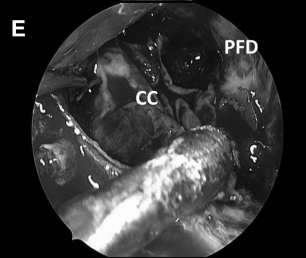

▼解剖、剥离并切除肿瘤包膜(D、E)

▼(L)使用鼻中隔瓣(NSF)完成封闭。CC,囊包膜;PFD,后颅窝硬脑膜;S,蝶鞍;T,肿瘤。